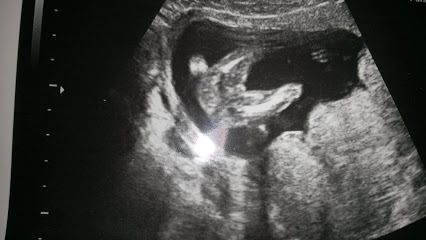

Mon calendrier de grossesse la 15ème semaine de grossesse (17 SA) 4ème mois Le premier mouvement ressenti est variable d'une femme à La 15e semaine de grossesse correspond à 17 semaines d'aménorrhée (SA) Notre corps continue à changer et on est maintenant très à l'étroit dans nos vêtements La croissance de notre bébé se poursuit, elle aussi, tout doucement © Eraxion Sommaire Côté bébé Le développement du bébé pendant la semaine 15 de grossesseSunt o gravidutza in 13 sapt si 5 zile si deja de cateva zile simt usoare miscari are lui bebeAm fost mirata pentru ca la prima sarcina am simtit miscari la 1718 saptamaniMama mia spus ca nu am cum sa simt miscari atat de devreme dar eu sunt absolut sigura este exact in dreptul uterului si am simtit exact ca la prima sarcina,un